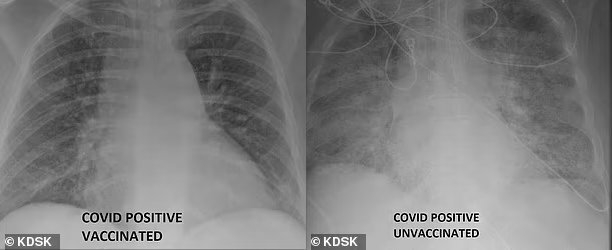

백신 접종한 코로나19 확진자의 폐(왼쪽)와 비접종 확진자의 폐(오른쪽)가 보인 엑스레이(X-Ray). 미국 방송국 KDSK

미국의 한 의사가 신종 코로나바이러스 감염증(코로나19)에 확진된 환자의 엑스레이(X-Ray) 사진을 공개하며 ‘백신의 중요성’을 증명했다.

2일(현지시간) 영국 매체 데일리메일에 따르면 미국 미주리주 세인트루이스대학병원 특수치료시설(ICU) 소속 가산 카멜 박사는 코로나19 백신을 맞지 않은 채 확진된 환자와 맞은 채 돌파 감염된 환자의 폐를 비교했다.

깨끗한 모습을 보인 백신 접종한 환자의 폐(왼쪽)에 비해 뿌옇게 나타난 비접종 환자(오른쪽)의 폐. 미국 방송국 KDSK

카멜 박사는 현지 언론과의 인터뷰에서 “백신이 만들어내는 차이를 보여주기 위해 이 엑스레이 사진들을 공개했다”며 “백신 접종을 하지 않은 코로나19 환자는 약물치료와 인공호흡기, 호흡을 위한 삽관 등 생명유지 장치를 필요로 할 수 있다”고 설명했다.